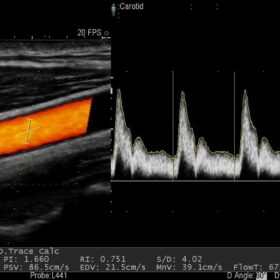

- Blood flow information can be easily acquired. The sharply delineated Doppler waveform is easy to measure.

- The Auto Trace function of Doppler waveforms supports exam efficiency significantly reducing the number of required key strokes.